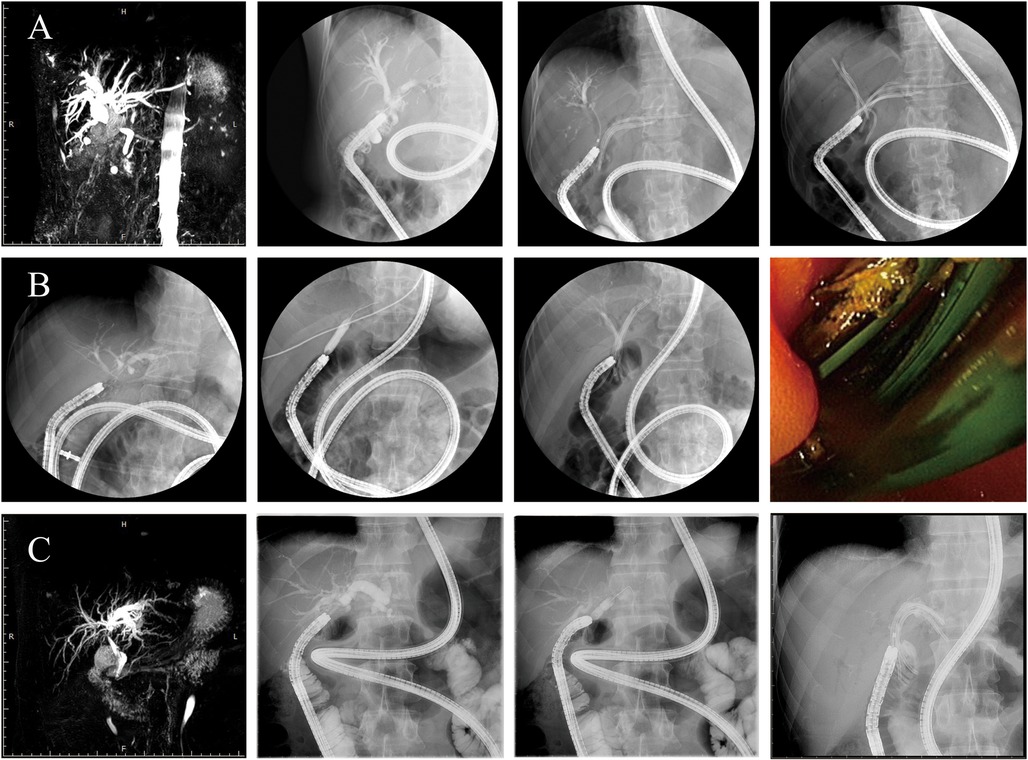

Details of initial therapy by SBE-ERCP

For the original course of treatment, all CJS and HJS patients received single-balloon endoscopies (Figure 2). Table 2 shows the details of the SBE-ERCP procedure and findings. A balloon dilation catheter was used to treat 29 (64.4%) of the 43 patients, and a Soehendra dilation catheter was used to treat 5 (11.6%) of the patients. We used a 12-mm balloon dilation catheter in 10 patients (23.3%) of the 29 patients who received balloon dilation for anastomotic stenosis. We dilated 22 patients (51.2%) to a diameter <10 mm. Moreover, we dilated 24 patients (70%) until the waist of the anastomotic site resolved, and in 10 patients (29.4%), the anastomotic waist remained. We performed bile duct stone extraction in 24 patients. During a median follow-up of 1.4 years, we carried out a total of 135 ERCP procedures on the 45 patients who made up the research sample (excluding the final ERCP or upper endoscopy for stent removal). In our 83 ERCP procedures, we conducted endoscopic stenting, with 2 (1.5%) consisting of the placement of a single stent and 81 (60%) consisting of the placement of multiple stents (range, 2–4). We used stents with a diameter of 7–10 Fr and a length of 10–15 cm, with stents sized at 8.5 Fr × 10 cm being the most common. The complications included post-ERCP pancreatitis in 7 patients and postsphincterotomy bleeding in 2 patients. We managed these conditions conservatively. The median time from stent placement to removal was 105 days (range, 14–500).

Figure 2

Grouped images of medical scans showing different stages of a procedure using radiographs and endoscopic images. Panel A displays various stages of a biliary intervention with contrast highlighting ducts. Panel B similarly shows stages within another procedure, with loops of tubing visible. Panel C shows a radiograph of biliary anatomy and tubing in place. One endoscopic image gives a direct visual of an internal area.

Figure 2. Operation procedure. The endoscopist collaborated with the nurse to inflate the scope and overtube as well as deflate and move the equipment, which were repeated to slowly advance the scope forward. Patients (A–C) represent three representative cases. In patient (A), endoscopic cannulation revealed common bile duct stricture (CJS), and after balloon dilation, biliary stents were placed in both the left and right hepatic ducts. In patient (B), no balloon dilation was performed; successful cannulation was followed by direct placement of a biliary stent. In patient (C), cannulation revealed a stricture at the left hepatic duct anastomosis, and after balloon dilation, a stent was placed in the left hepatic duct. Biliary duct cannulation was completed, and cholangiography revealed CJS/HJS. The bilioenteric Roux-en-Y anastomotic stricture was treated by balloon dilatation.